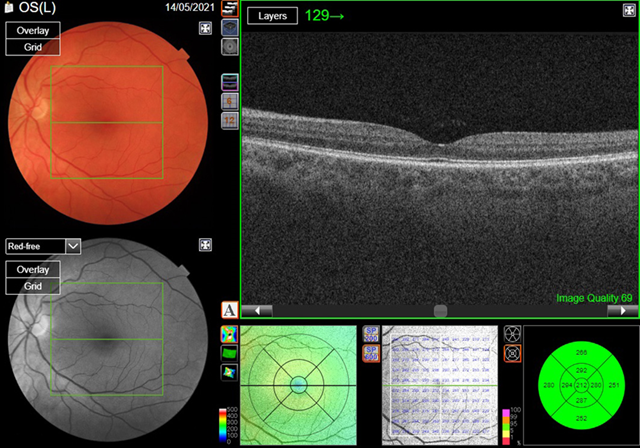

Optical

coherence tomography (oct) is a non-invasive imaging modality that uses

low-coherence light to capture micrometer resolution images of the retina.

Using the information obtained, two and three dimensional images of the retina

are formed which the clinician can use to give an indication of retinal/ rpe

health. The case study patient’s macula oct scans were normal (figures 3a,3b).

(a) Right eye

(a) Left eye

Figure

3.

Optical coherence tomography

(oct)